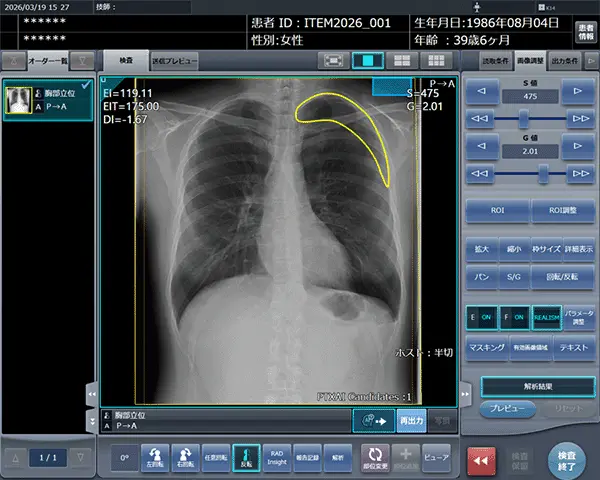

コンピューターのスクリーンショット

「CXR Finding-i 気胸検出タイプ」により解析された気胸の検出領域を表示

「STAT Link」は、気胸検出機能、所見報告・記録機能、「RADInsight(ラドインサイト)」との連携機能により、STAT画像所見報告のワークフローを包括的に支援します。

■気胸検出機能(「CXR Finding-i 気胸検出タイプ」との連携)

気胸の診断支援を行うプログラム「CXR Finding-i 気胸検出タイプ」と連携することで、ガイドラインにおいて一般撮影で診療放射線技師が発見した場合に報告すべきSTAT画像所見の一つに挙げられている気胸の候補を高精度で検出することができます。